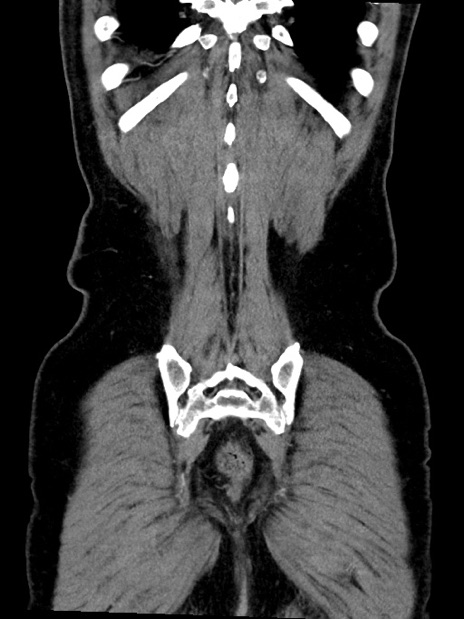

症例35(冠状断像)

【症例】70歳代 男性

【主訴】腹部膨満、嘔吐

【現病歴】昨日より腹部膨満感出現。本日増悪し、仙痛出現。嘔吐あり、受診。

【既往歴】糖尿病、胆摘後

【身体所見】BP 149/80mmHg、HR 74/min、BT 35.9℃、腹部:膨満、軟、圧痛なし。腸雑音減弱あり。上腹部正中切開瘢痕あり。

【データ】WBC 13500、CRP 1.72